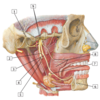

#1 - lateral pterygoid muscle

#1 - medial pterygoid muscle

#1 - ciliary ganglion

#2 - short ciliary nerves

#3 - inferior division of oculomotor nerve

#4 - pterygopalatine ganglion

#5 - abducent nerve (CN VI)

#6 - ophthalmic nerve (CN V1)

#7 - oculomotor nerve (CN III)

#8 - trochlear nerve (CN IV)

#1 - trochlear nerve (IV)

#2 - opthalmic nerve (V1)

#3 - optic nerve (II)

#4 - oculomotor nerve (III)

#5 - abducent nerve (VI)

#6 - trigeminal (semilunar) ganglion

#7 - frontal nerve

#8 - lacrimal nerve

#9 - supra-orbital nerve

#1 - auriculotemporal nerve

#2 - chorda tympani nerve

#3 - lingual nerve

#4 - inferior alveolar nerve (cut)

#5 - nerve to mylohyoid

#6 - mental nerve

#7 - submandibular ganglion

#8 - buccal nerve and buccinator muscle (cut)

#9 - mandibular nerve (V3) (anterir and posterior division)